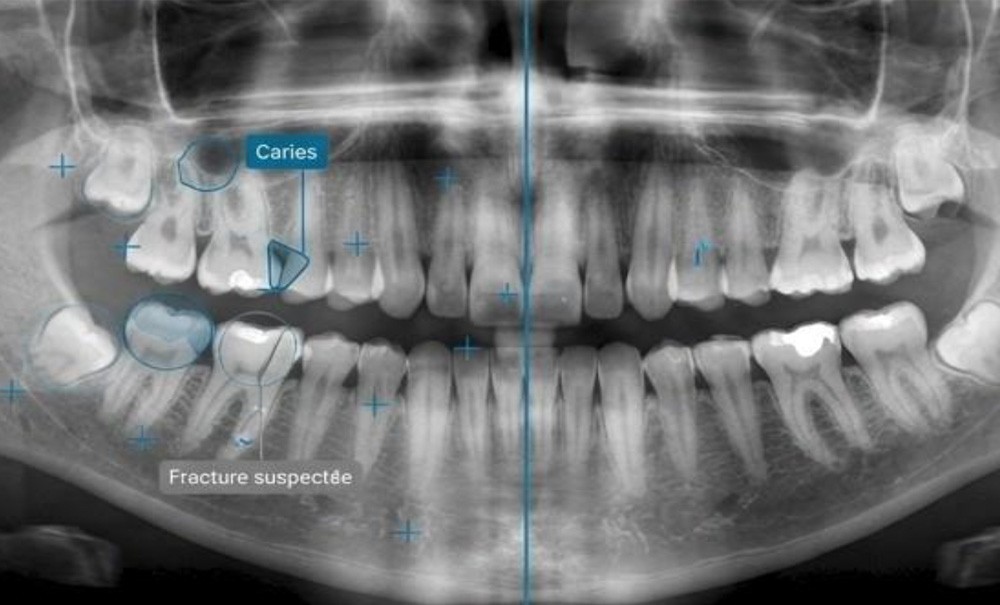

En orthodontie, la modernité n’est pas une incantation : c’est une démarche scientifique et clinique qui exige des compétences, de la méthode, de l’éthique et du discernement. L’IA et le numérique sont des outils (fig. 1) ; mal utilisés, ils deviennent des dangers !

L’IA peut être précieuse, à condition d’être comprise et contrôlée. Elle ne « voit » pas tout : elle analyse certains paramètres et produit des résultats probabilistes. Elle ne « sait » pas ; elle calcule. Dès lors, il faut être…